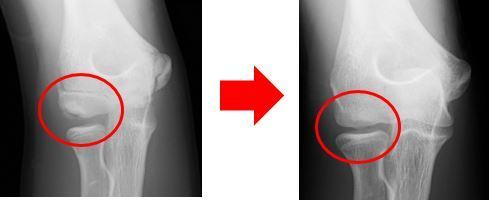

下の画像では、初診時のものでは上腕骨小頭の分離を認めます。

6か月後のレントゲン画像では分離した骨がきれいに治っています。

初診時 6ヶ月後